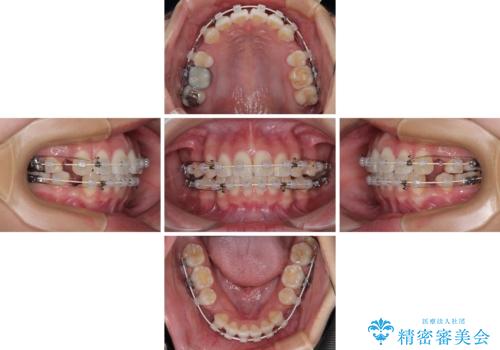

- 矯正装置

- 審美装置

- 前歯が突出して、眠るときに口が開いてしまうことを気にして来院された患者様です。

横から見た際の口元の飛び出した印象も改善したいとのことで、上下左右の第一小臼歯4本を抜歯し、ワイヤー装置にて抜歯矯正を行うこととしました。

舌の突出癖改善のためのトレーニングをしっかりと実践してくださり、2年強の治療期間でしっかりと仕上げることができました。